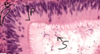

Pineal gland - pinealocytes, interstitial cells, brain sand

Pineal gland: made of nervous tissue, nuclei belong to one of 2 cell types. Larger nuclei that stain lighter belong to pinealocytes (make melatonin). Darker, elongated nuclei are interstitial cells. Brain sand (aggregates of calcified secretions and calcified ECM)

Pineal gland: pinealocytes, brain sand ( corpora arenacea )

Pinealocytes of pineal gland